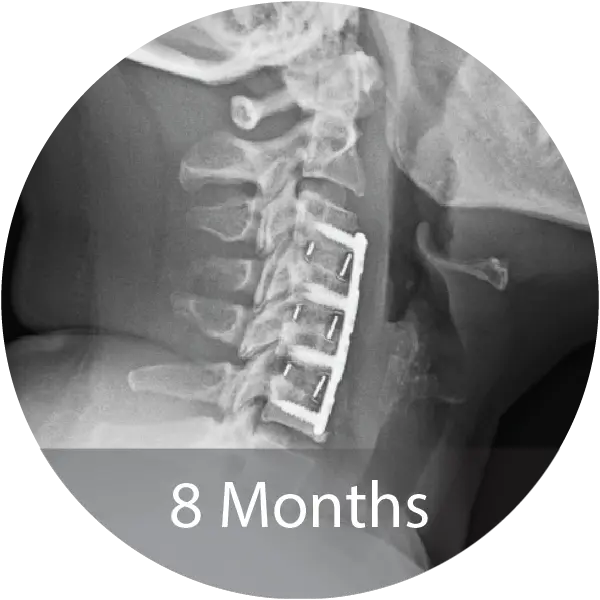

Case of an 80-year-old female with cervical degenerative disc disease and stenosis treated with a 3-level ACDF using NMP® Fibers. Reported 12-month fusion, no adverse events, complete pain resolution, and excellent handling characteristics.